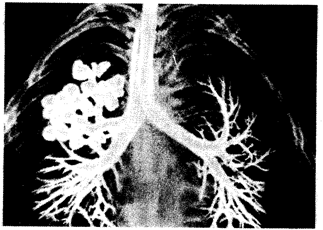

Рис. 14.26. Кистозная гипоплазия легкого